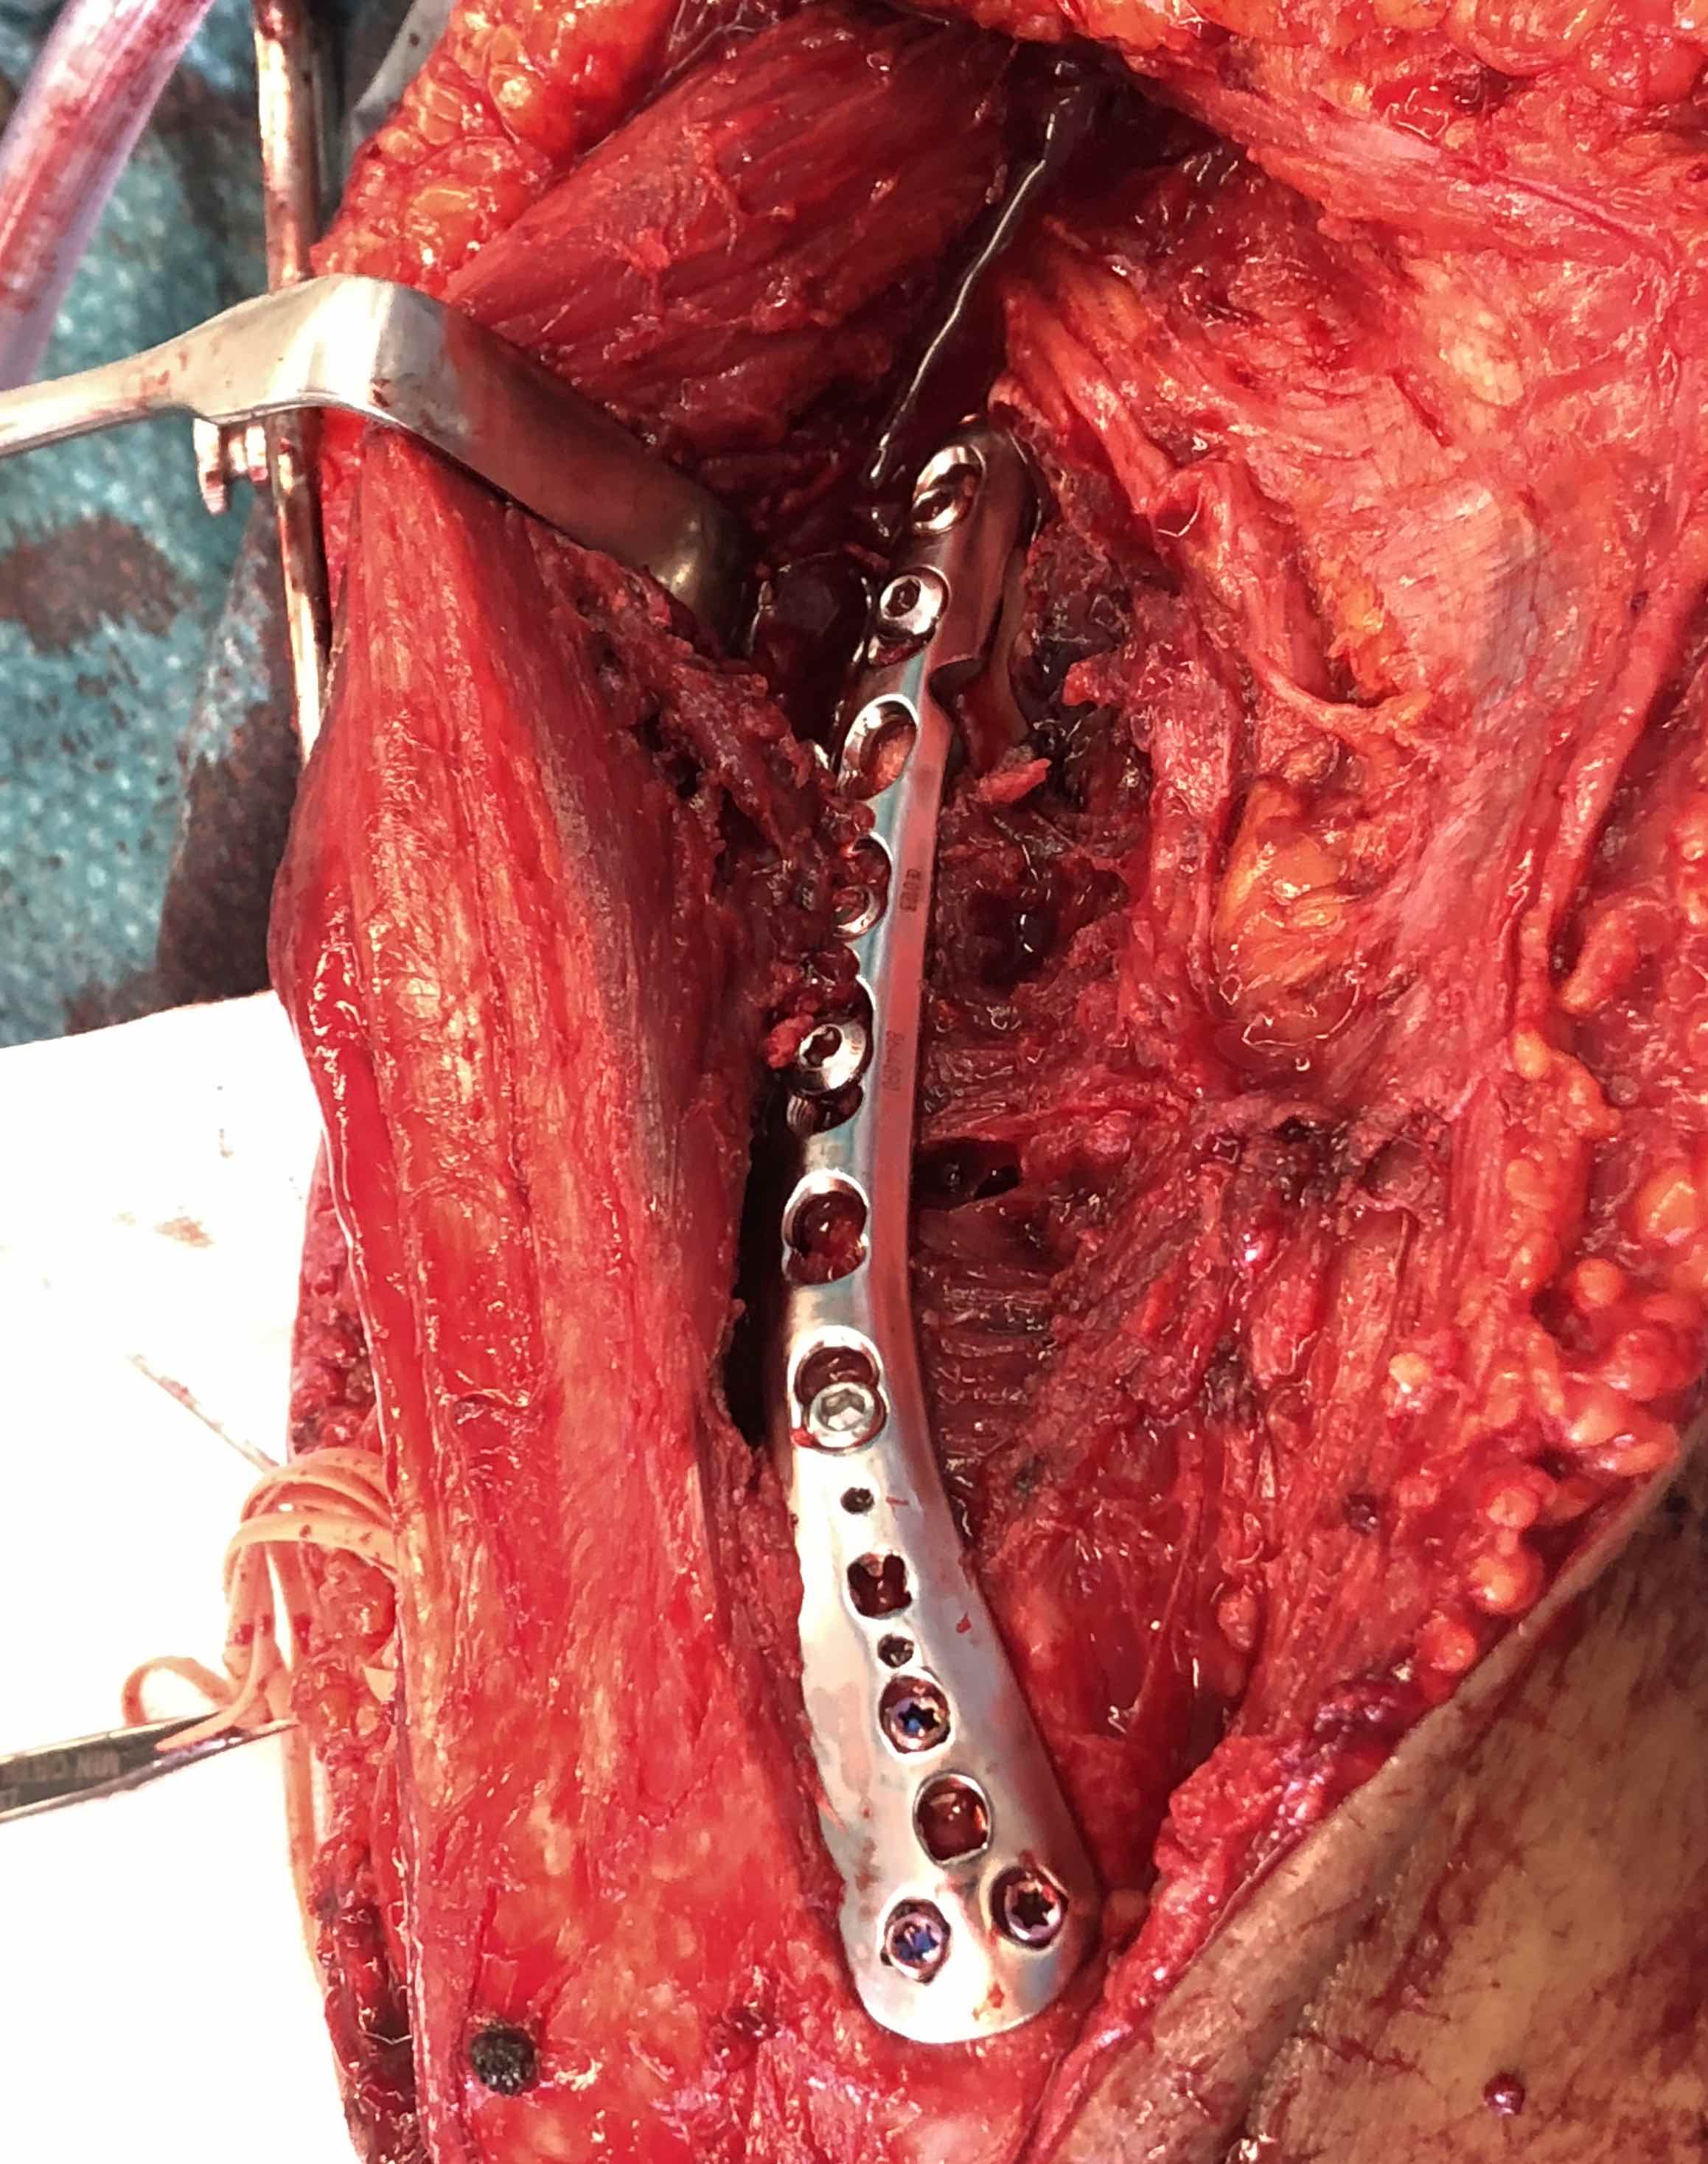

Humeral Fracture SegmentalHumeral Plate LateralHumeral Plate Long AP

Segmental fracture ORIF

Prox humerus 1Prox humerus 2Prox humerus ORIFProximal humerus ORIF

Proximal third humerus ORIF of nonunion